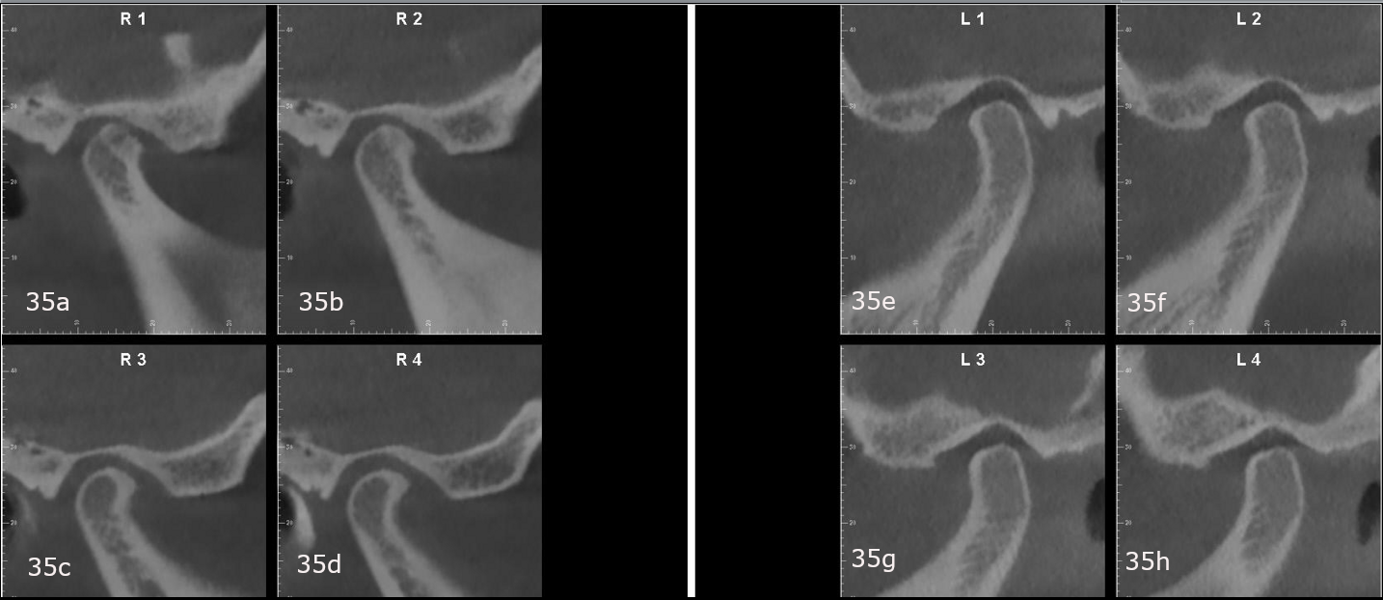

The panoramic radiograph showed slight bone loss, the presence of the maxillary third molars and mandibular left third molar and correct root morphology (Fig. 33). In the cephalometric radiograph and tracing, a Class II skeletal pattern and a marked negative torque of the maxillary incisors were observed (Fig. 34). The CBCT scan of the condyles showed that both condyles were well corticated, although the right condyle had undergone a process of PCR with reparation, evident from the good corticalisation and osteophyte (Fig. 35). This resorption process had affected the ramus, the right mandibular ramus being shorter than the left. This perfectly explained the reason for the patient’s mandibular deviation. We also observed a lack of functional space around the right condylar head, which was a clear sign that there was probably no disc present.